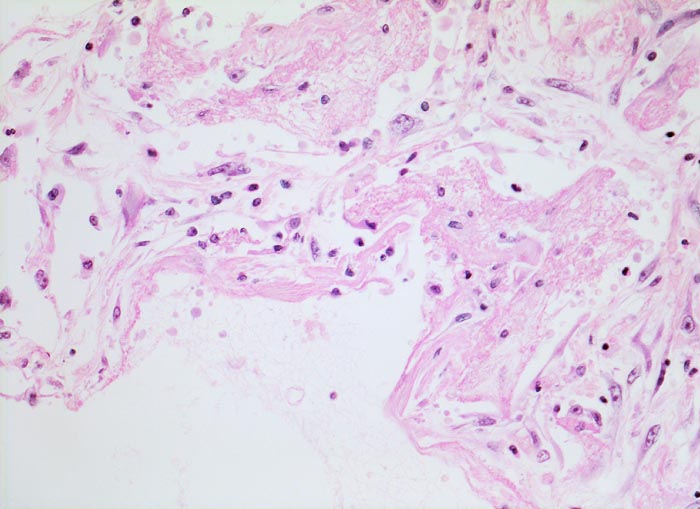

Diffuser Alveolarschaden: hyaline Membranen

Die Alveolarwand ist austapeziert mit einer homogenen, eosinophilen hyalinen Membran. Die hyaline Membran besteht aus fibrinreicher Ödemflüssigkeit gemischt mit Bestandteilen nekrotischer Epithelzellen. (= exsudatives Stadium der fibrosierenden Alveolitis). Die aufgelockerten Alveolarwände enthalten Fibroblasten und Makrophagen.

Bei der hyalinen Membranenkrankheit des Neugeborenen (IRDS) handelt es sich trotz morphologischer Ähnlichkeit mit den hyalinen Membranen der fibrosierenden Alveolitis um eine andere Erkrankung (mangelnde Surfactantbildung).